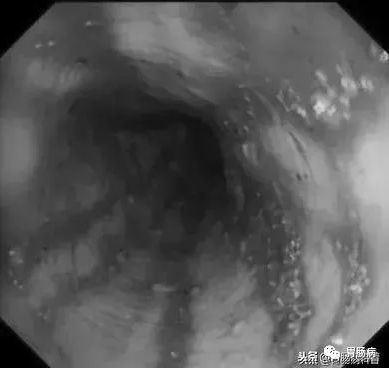

進鏡后在食道內(nèi)可見血凝塊及少量血液,食道及賁門未發(fā)現(xiàn)靜脈曲張及賁門撕裂。

胃內(nèi)可見大量的暗紅色血液及血凝塊潴留

我們再次返回食道內(nèi),發(fā)現(xiàn)持續(xù)有少量鮮血附著于管壁上,邊退鏡邊沖洗,在食道入口處發(fā)現(xiàn)血液量增多,但因食管上括約肌及環(huán)咽肌收縮,入口處黏膜觀察不清,后在胃鏡前端使用透明帽后,視野改善很多。

如下圖:

在食道入口,距門齒約18至20cm處可見片狀黏膜剝脫及條索狀裂傷,持續(xù)滲血。